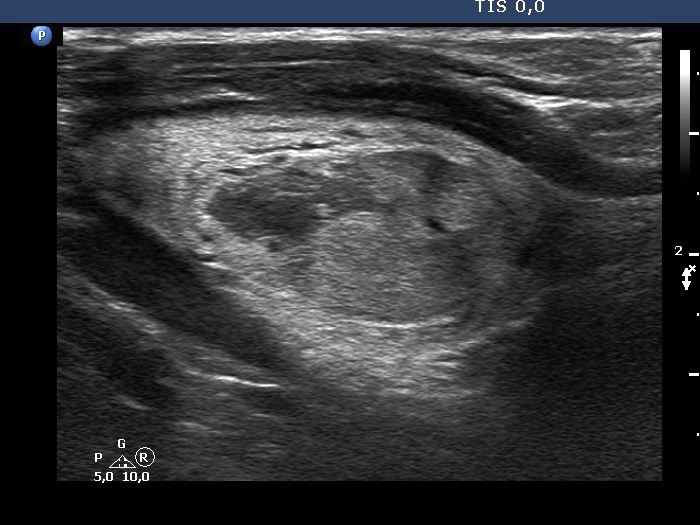

Examination one year later (ultrasonographic picture 8)

Right lobe, longitudinal scan